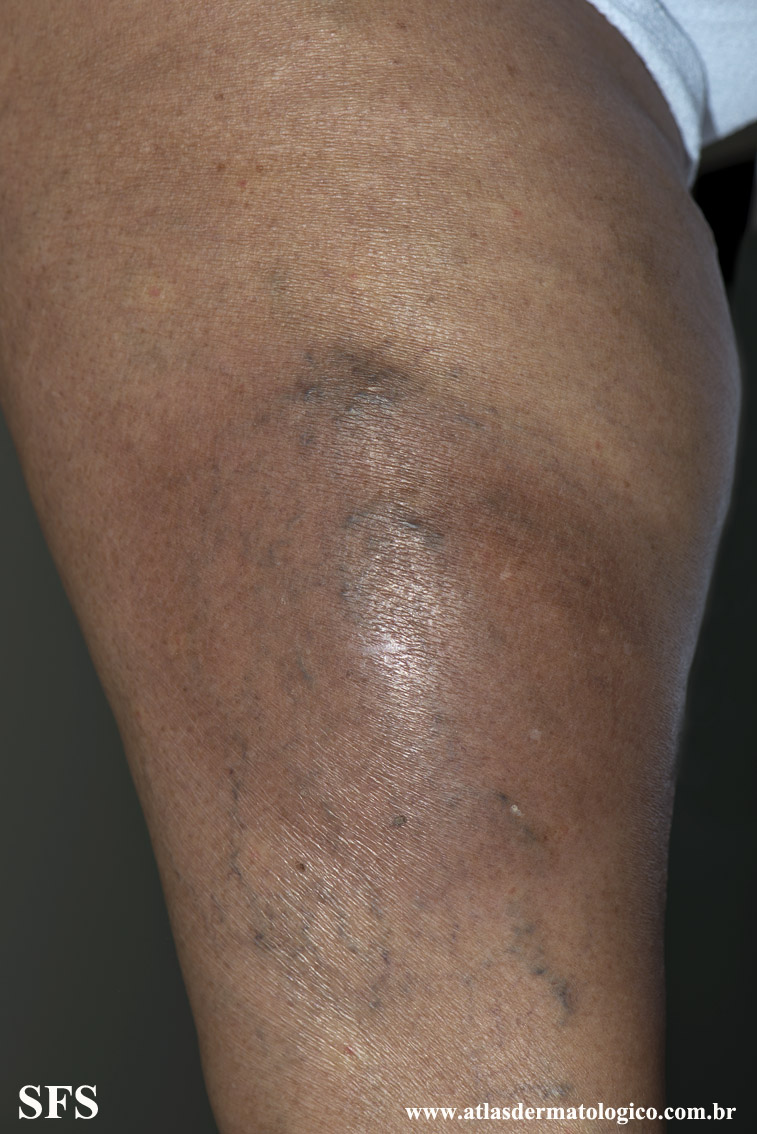

lipodermatosclerosis